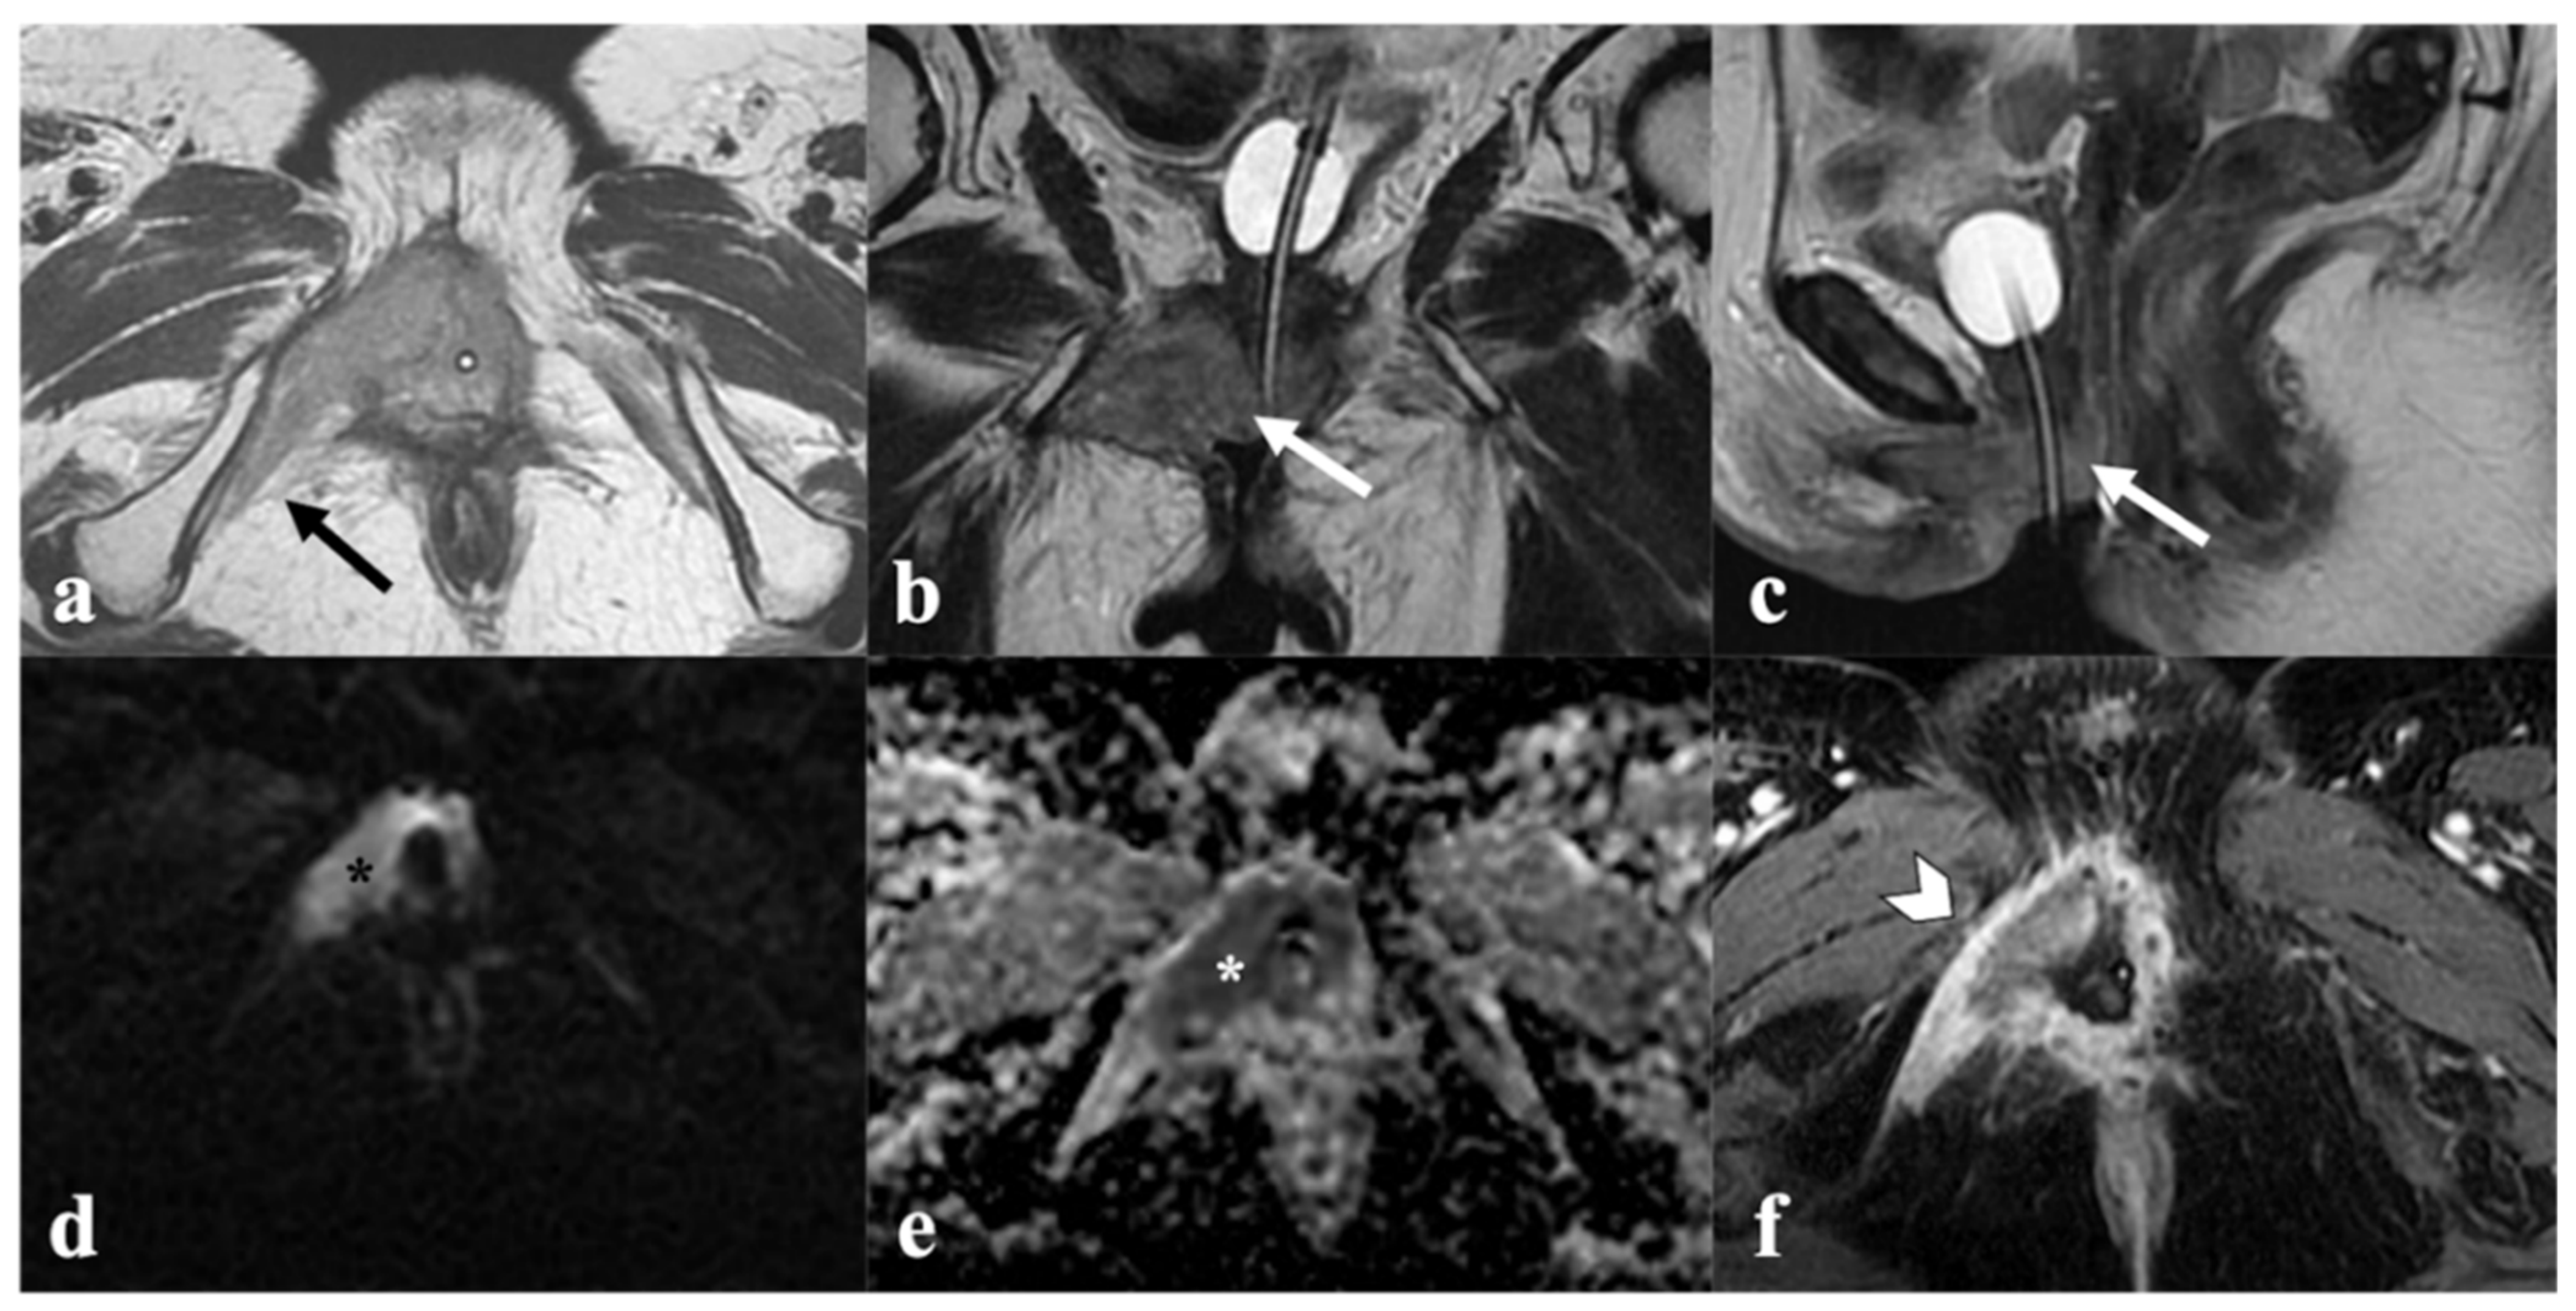

5. Vulvar Cancer Recurrence

6. Post-Therapy Complications

4.1. Local Tumor Status and Residual Invasion of Adjacent Organs

4.2. Lymph Node Status